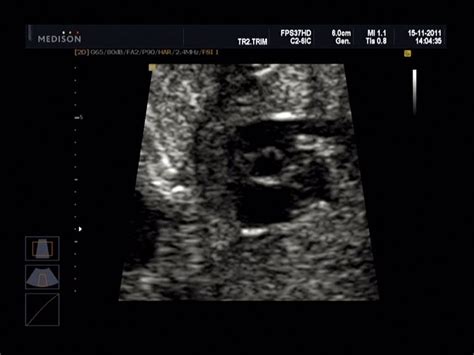

Spočiatku je vhodnejší transvaginálny ultrazvuk, čiže ultrazvuková sonda je zavedená do pošvy. Neskôr lekár prechádza na transabdominálny ultrazvuk, keď pozerá dieťatko cez brušnú stenu. Aj v neskorších štádiách tehotenstva však môže siahnuť ešte po transvaginálnom ultrazvuku, napríklad pri zisťovaní dĺžky krčka maternice. Ultrazvukové vyšetrenia v tehotenstve trvajú približne 10 až 30 minút - závisí od toho, či ide o bežný kontrolný malý ultrazvuk, ktorý lekár robí na každej tehotenskej poradni (môže trvať niekedy 3 až 5 minút), alebo je to „veľký“ ultrazvuk napríklad v 20. týždni.

- Transvaginálny ultrazvuk: V skorých štádiách tehotenstva, najmä v prvom trimestri, je vhodnejší transvaginálny ultrazvuk. Pri tomto type vyšetrenia sa ultrazvuková sonda zavádza do pošvy, čo umožňuje lepšiu vizualizáciu embrya a vnútorných orgánov.

- Transabdominálny ultrazvuk: Neskôr, keď je plod väčší, sa prechádza na transabdominálny ultrazvuk. Lekár pri tomto vyšetrení prechádza sondou po brušnej stene matky, pričom na brucho nanesie priehľadný gél pre lepšiu vodivosť.

Samotné ultrazvukové vyšetrenie je nebolestivé. Pri transabdominálnom ultrazvuku lekár nanesie na brucho gél a pomocou sondy jemne prechádza po brušnej stene. Pre lepšiu viditeľnosť sa pri tomto type vyšetrenia odporúča mať plný močový mechúr. Pri transvaginálnom ultrazvuku lekár nanesie gél na ultrazvukovú sondu, na ktorej je z hygienických dôvodov zvyčajne natiahnutý kondóm, a sondu opatrne vsunie do vagíny.